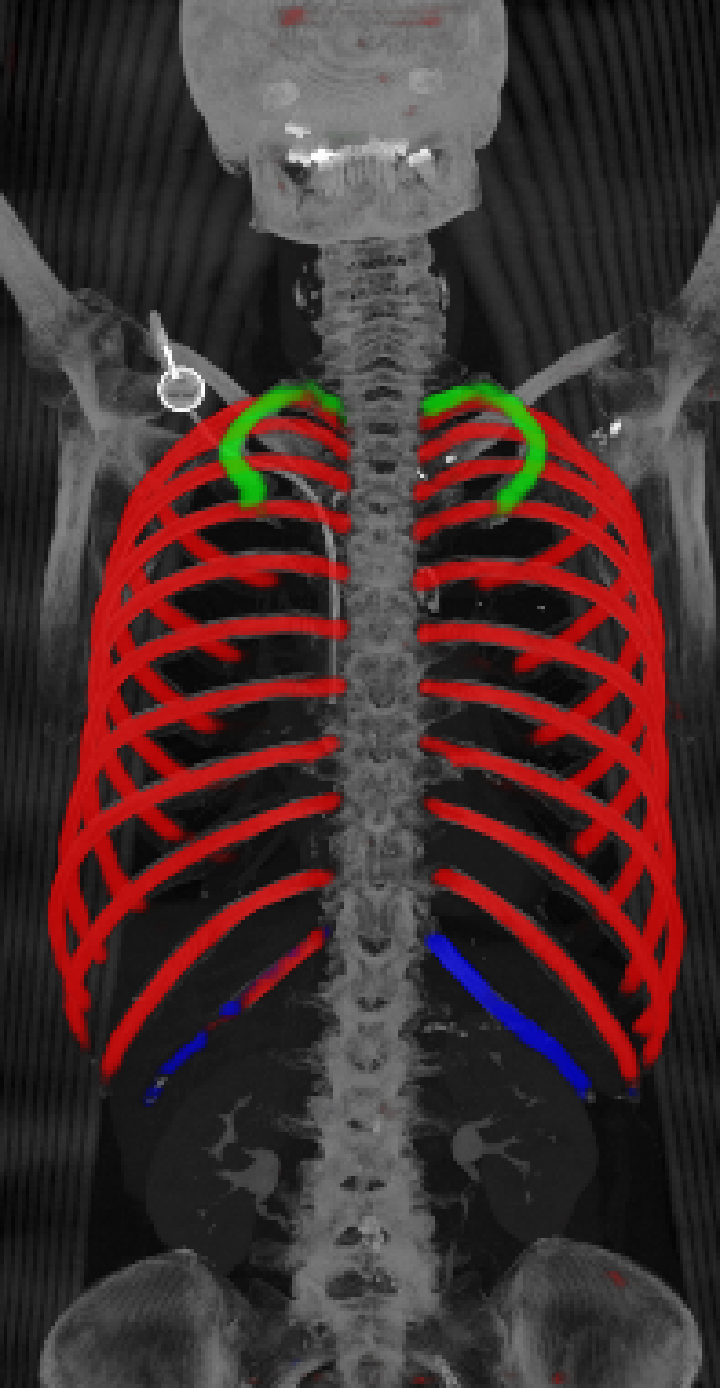

As can be seen from Table 2, we obtain overall good performance for the overall rib detection captured for example with an mean Dice of 0.84. Let us remark that for thin objects, such as the dilated rib centerlines, the Dice score constitutes a rather sensitive measure. The results indicate that detecting the first and twelfth rib pairs is more difficult for our network. While extraction of the first rib is more challenging due to, e.g., higher noise in the upper thorax or other bony structures in close vicinity (clavicle, shoulder blades, vertebrae), the twelfth rib can be extremely short and is easily confused by the neighboring ribs. For further illustration, Figure 4 shows the results on selected representative cases. Generally, the ribs are well detected without major false responses in other structures - despite all the different challenges present in the data. The color coding highlighting of the multi-label detection reveals that first and twelfth are mostly correctly detected. In few cases the network wrongly generated strong responses of the classes first rib or last rib for voxels belonging to the second or eleventh rib pair.

Refer to caption

Figure 4: Maximum intensity projections (MIP) of selected CT volumes overlaid with the multi-label output of the neural network (green: first rib; red: intermediate rib; blue: twelfth rib). The selected case above display common difficulties which are inherent in the data set, such as pads (a) or cables (b), internal devices such as pacemakers (c), stents (d), spinal (e) and femural/humeral implants (f), injected contrast agents (g), patient shape variations such as scoliosis (h), limited field of views (FOVs), i.e. partly missing first (i) or twelfth rib (j).